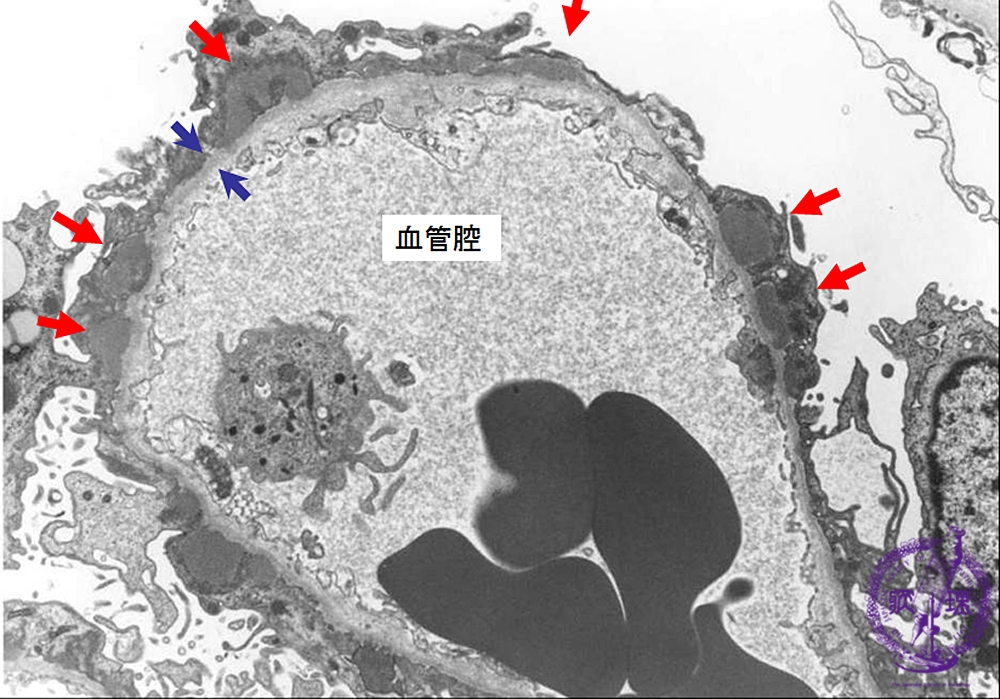

- ★(2)Membranous nephropathy

Electron microscopic findings: Stage I: Subepithelial electron dense deposits are observed (red arrows). The basement membrane is not thickened(blue arrows).